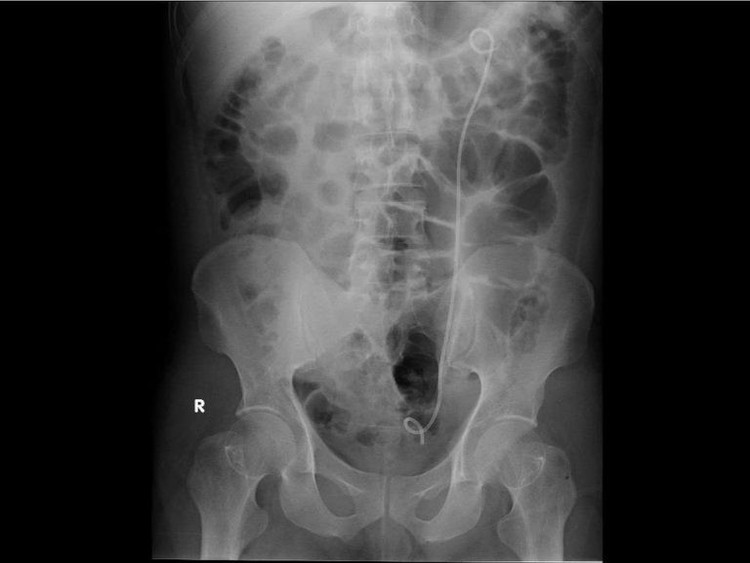

Hình ảnh cận lâm sàng sau khi đặt Sonde JJ dẫn lưu - Ảnh BVCC

Ê-kíp các bác sĩ khoa Ngoại tiết niệu, Bệnh viện Đa khoa Xuyên Á và các bác sĩ cấp cứu đã nhanh chóng vừa hồi sức vừa chỉ định đặt thông JJ cấp cứu từ bể thận trái xuống niệu quản và bàng quang. Thủ thuật này nhằm giải phóng chỗ tắc nghẽn do sỏi, giúp nước tiểu và mủ trong thận được dẫn lưu ra ngoài, giảm áp lực và kiểm soát ổ nhiễm trùng.

Trong quá trình can thiệp, ê–kíp ghi nhận mủ chảy nhiều từ thận xuống bàng quang. Mủ được cấy để phân lập vi khuẩn giúp điều trị kháng sinh theo đúng loại vi khuẩn gây bệnh. Trong lúc chờ đợi kết quả các bác sĩ cũng sử dụng kháng sinh theo phác đồ điều trị nhiễm khuẩn nặng.